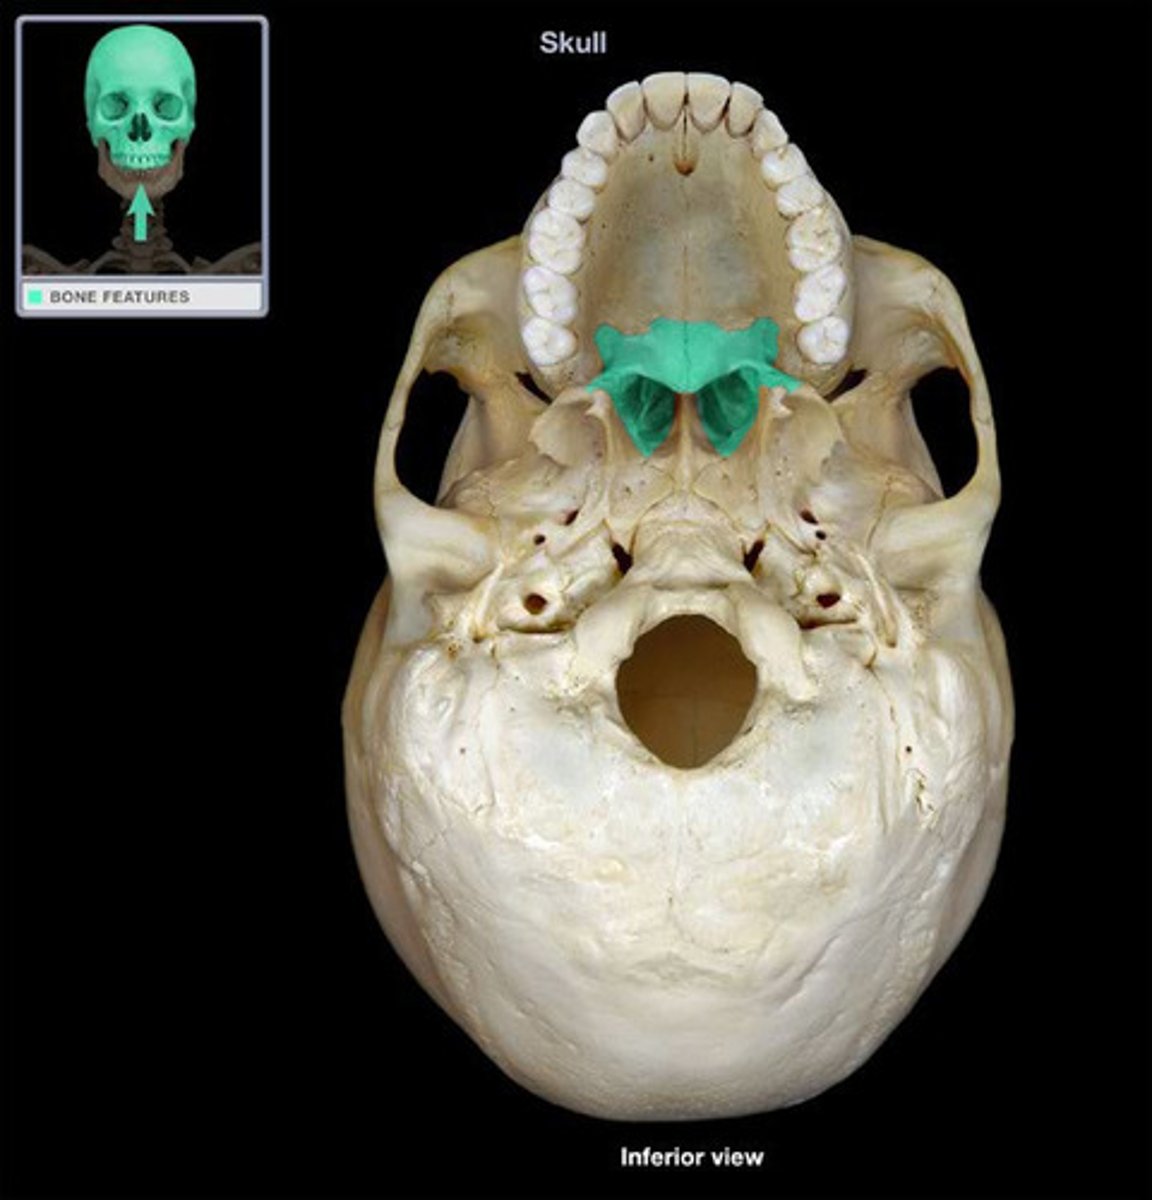

- Palatine bone

- two L-shaped bones composed of vertical and horizontal plates

- Horizontal articulates with maxillae

- Vertical portions extend upwards between maxillae and pterygoid processes of sphenoid in posterior nasal cavity

What is this and how is it formed ?